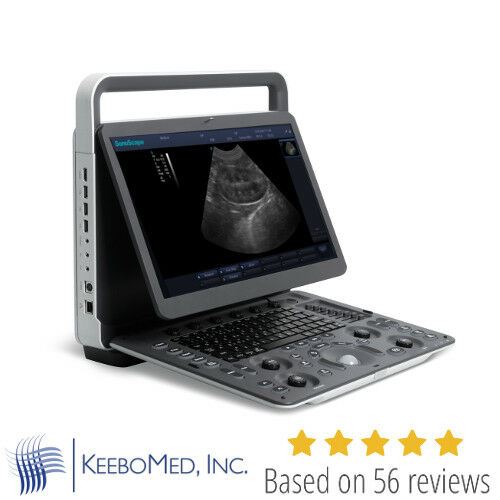

Save $ 1,106.79

DIAGNOSTIC ULTRASOUND MACHINES FOR SALE

Veterinary Ultrasound Sonoscape A6V Expert (E1V) With Rectal and Micro Convex

Sale price$ 5,042.04

Regular price$ 6,148.83